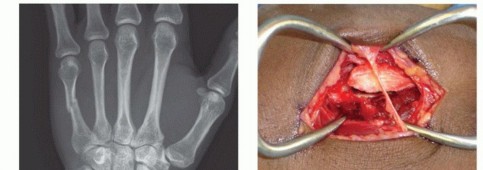

Clinical & Radiographic Imaging Archive